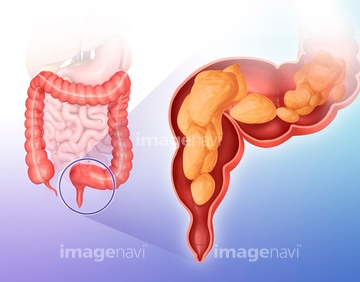

腰痛の原因となる 大腸がん 結腸がん 直腸がん とは 特徴 症状 治療

身体 腹部 直腸 結腸 生物学 理科 断面 の画像素材 写真素材ならイメージナビ

身体 腹部 直腸 結腸 生物学 理科 断面 の画像素材 写真素材ならイメージナビ

大腸がんとは 北青山dクリニック